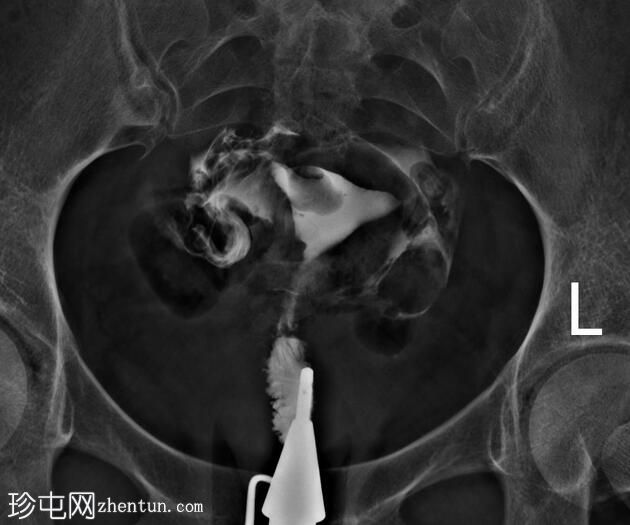

正位片

子宫内膜腔内可见一卵圆形充盈缺损,边缘光滑,强烈提示子宫内膜息肉的存在,生理盐水灌注子宫声学造影(未显示)证实了这一诊断。

鉴别诊断中还应考虑黏膜下肌瘤。